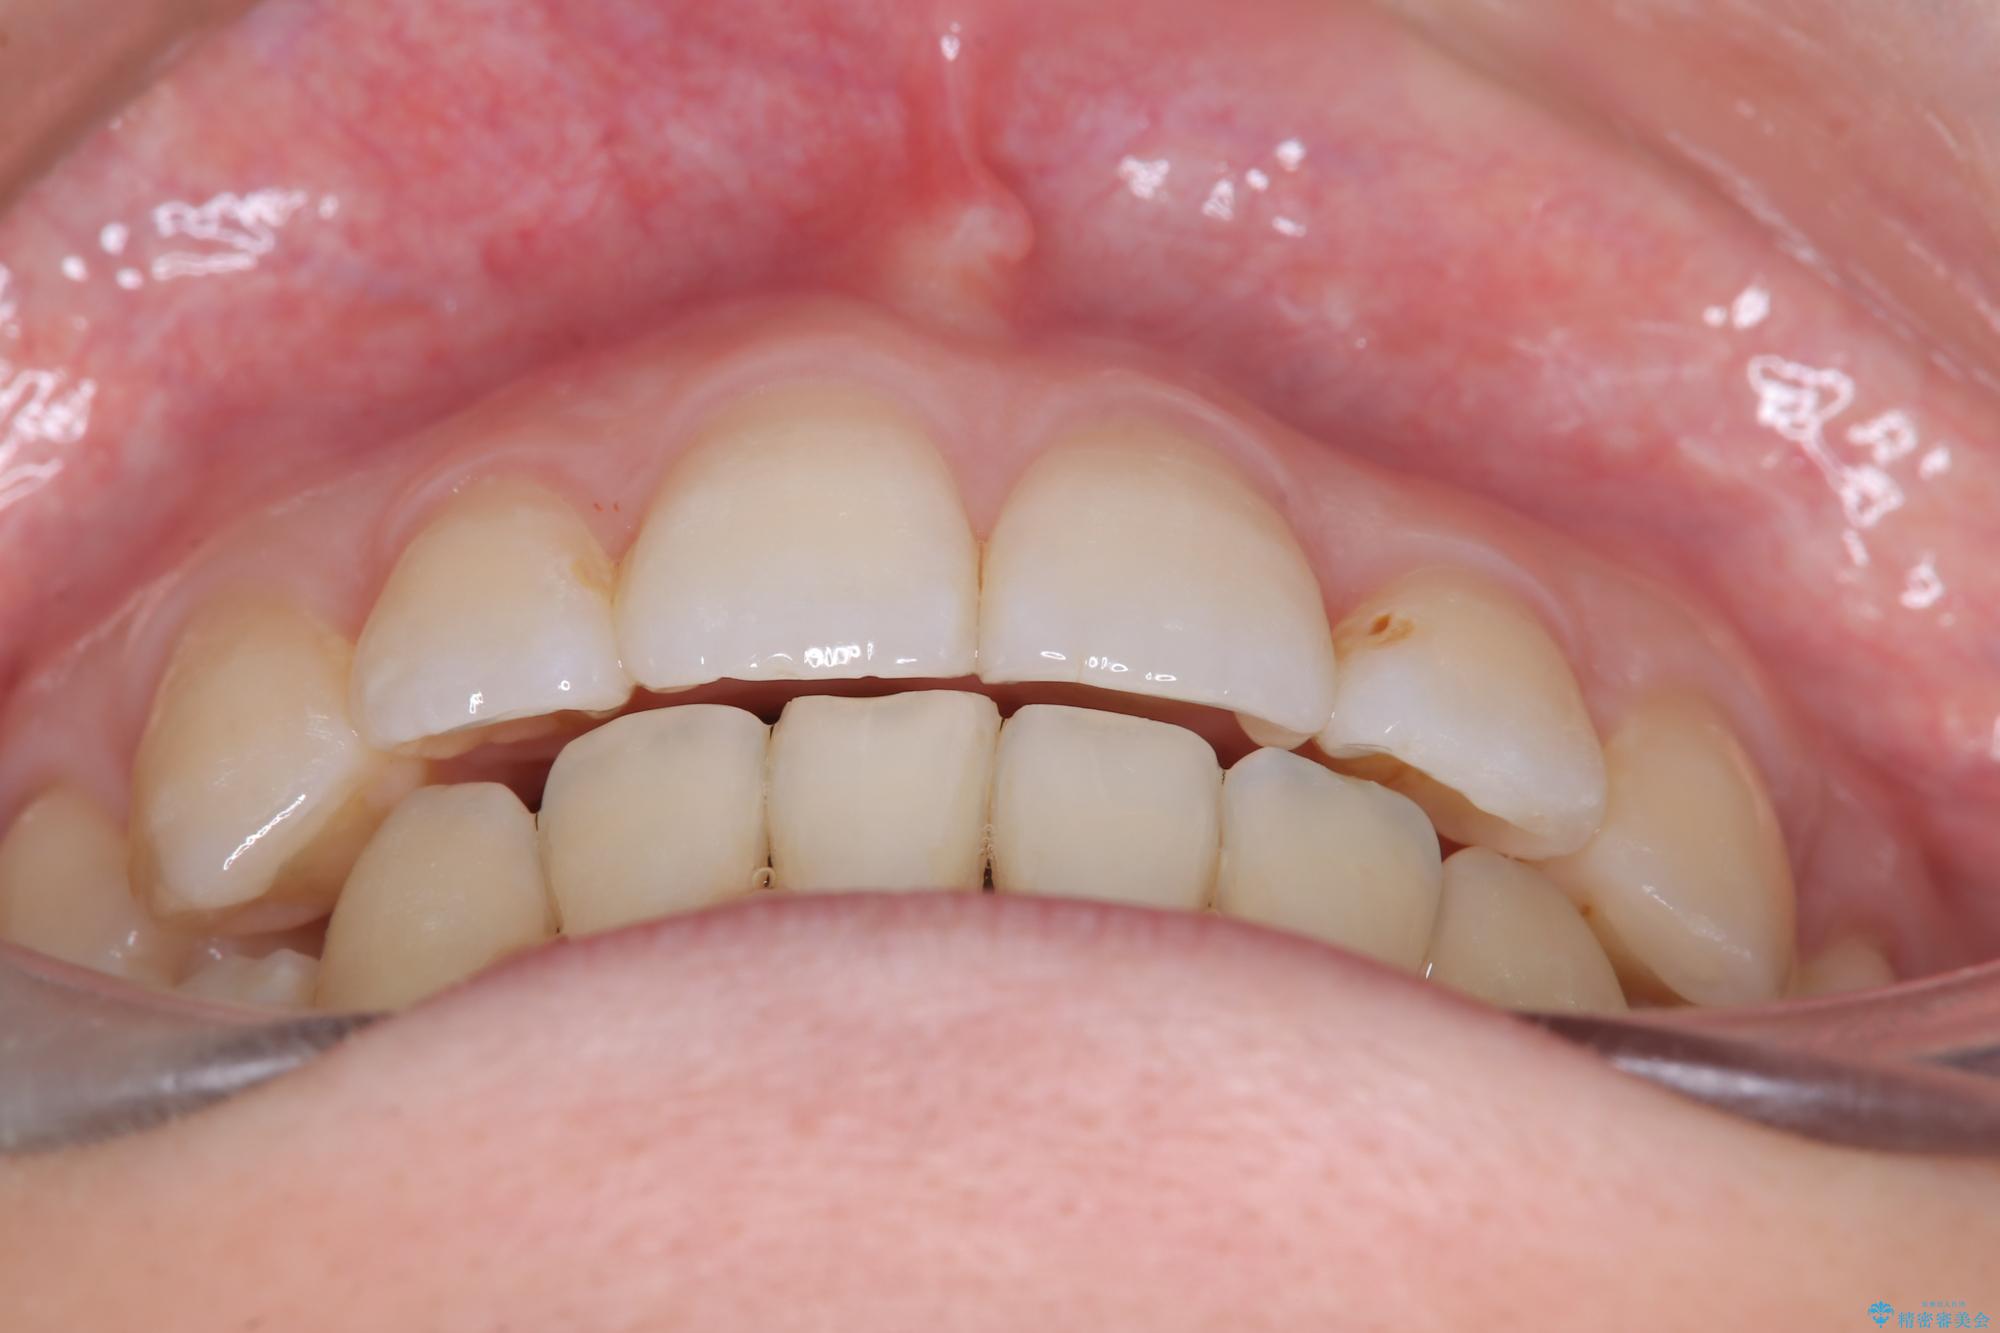

【ワイヤー矯正】口元を下げたい、下の歯の凹凸を無くしたい

- 主訴:口元を下げて前突感を無くしたい、下の歯の凹凸も無くしたい

右側第二小臼歯、左側第一小臼歯、下顎両側第一大臼歯を抜歯しワイヤ-矯正を行いました。

骨格的顎の変位を認めたため、顔貌に対しピッタリ上下の歯の正中を合わせることは難しいと説明し、上下左右計4本小臼歯を抜歯しワイヤー矯正治療を行いました。